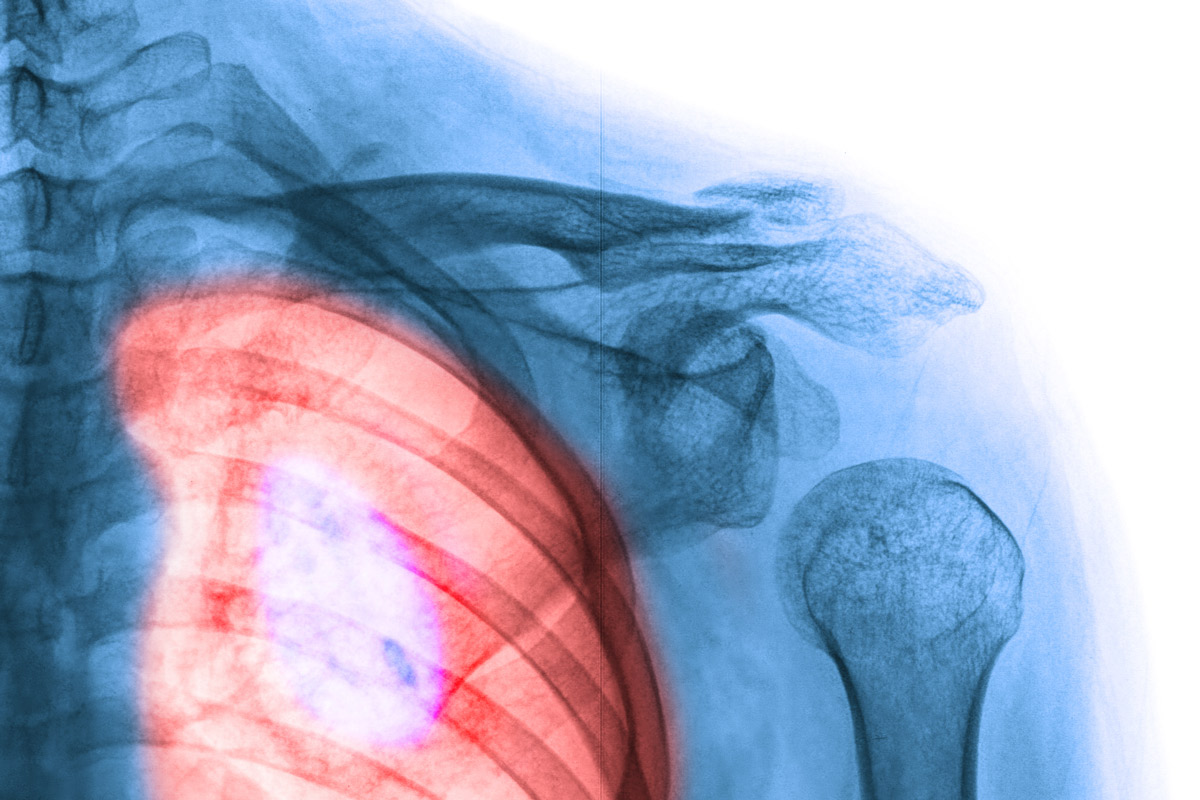

Lung Cancer Screening X Ray

Experience the clarity of Lung Cancer Screening X Ray with our curated collection of comprehensive galleries of images. featuring understated examples of photography, images, and pictures. designed to emphasize clarity and focus. Discover high-resolution Lung Cancer Screening X Ray images optimized for various applications. Suitable for various applications including web design, social media, personal projects, and digital content creation All Lung Cancer Screening X Ray images are available in high resolution with professional-grade quality, optimized for both digital and print applications, and include comprehensive metadata for easy organization and usage. Our Lung Cancer Screening X Ray gallery offers diverse visual resources to bring your ideas to life. Comprehensive tagging systems facilitate quick discovery of relevant Lung Cancer Screening X Ray content. Multiple resolution options ensure optimal performance across different platforms and applications. Time-saving browsing features help users locate ideal Lung Cancer Screening X Ray images quickly. The Lung Cancer Screening X Ray archive serves professionals, educators, and creatives across diverse industries. Instant download capabilities enable immediate access to chosen Lung Cancer Screening X Ray images. Whether for commercial projects or personal use, our Lung Cancer Screening X Ray collection delivers consistent excellence. Professional licensing options accommodate both commercial and educational usage requirements.